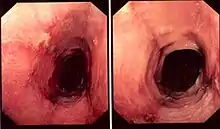

Pathology image of lymphocytic esophagitis (H&E stain). The image demonstrates common findings in the condition: dense peripapillary lymphocytic infiltrate with spongiosis (arrow), and absence of neutrophils and eosinophils. | |

While the diagnosis of lymphocytic esophagitis depends on the biopsy results, certain changes can be visualized directly at the time of endoscopy. The esophagus may be narrow in calibre,[5] may show multiple rings,[5] redness,[5] linear furrows[1] or the mucosal lining may slide demonstrating a "crepe-paper" appearance.[1] Complications such as strictures of the esophagus can also be detected with endoscopy.[5] These changes are very similar to those found in eosinophilic esophagitis, a more common and better understood esophageal disorder thought to be of allergic origin.[5] Narrow-band imaging with magnification endoscopy is another imaging modality that can show characteristic changes of lymphocytic esophagitis.[7]